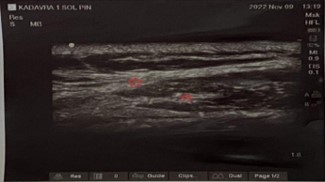

A 49-year-old female patient applied to the medical oncology unit in August 2019 due to a mass in her left breast. After the necessary tests, invasive breast cancer was detected in the biopsy, and breast-conserving surgery was performed. Afterwards, 3 cycles of docetaxel + cyclophosphamide chemotherapy and a total of 60 Gy radiotherapy in 30 fractions were given. Recurrence occurred in the same area in September 2020. After 4 cycles of doxorubicin + cyclophosphamide and 12 cycles of paclitaxel, modified radical mastectomy was performed, and oral capecitabine was started. Approximately one year later, recurrence was detected in the cervical and supraclavicular regions, and 45 Gy radiotherapy in 20 fractions and 6 cycles of gemcitabine were applied. Four weeks after the last chemotherapy, redness, pain, and swelling developed in the left supraclavicular region. In the evaluation made by medical oncology, weakness was detected in the left shoulder and upper extremity. She was referred to our pain clinic for the preliminary diagnosis of radiation-induced brachial plexopathy and pain palliation. On examination, neck deviation to the left, increased left shoulder height, and Sternocleidomastoid (SCM) muscle contracture were detected. Right neck rotation limitation, severe pain on palpation of the neck region, and color change were observed. In addition, there was moderate loss of strength in shoulder abduction and arm extension on muscle strength examination (Figure 1). McGill pain score was 92, and Visual Analog Scale (VAS) score was 9 points. In our Ultrasonography (USG) evaluation, we observed hyperechogenicity in the SCM, trapezius, and scalene muscles (Figure 2). In magnetic resonance imaging, we observed hyperintensity in the T2 phase and contrast enhancement in T1 in the same muscle groups (Figure 3). Gemcitabine treatment was stopped with the diagnosis of gemcitabine-associated radiation recall myositis. We started the treatment with drugs such as prednisolone, ibuprofen, and paracetamol + tramadol. However, despite 5 weeks of treatment, the symptoms did not regress. A 70% loss in sleep quality and daily life activities was observed due to pain. We applied dexamethasone and lidocaine to the SCM, trapezius, and scalene muscles under USG guidance. VAS decreased from 9 to 7 within a week. Afterwards, 100 IU abobotulinum toxin A was applied to the same muscles [8]. After one month, the VAS score decreased to 2. The need for analgesics decreased to 2 tablets of ibuprofen in the last month. The contracture almost completely resolved (Figure 4). The McGill score was measured as 20. Written informed consent was obtained from the patient for publication of this case report and accompanying images.

Figure 2: On ultrasonographic imaging, thickening of the fascia of the sternocleidomastoid muscle and hyperechoic areas caused by disruption of muscle tissue homogeneity are indicated with red stars.